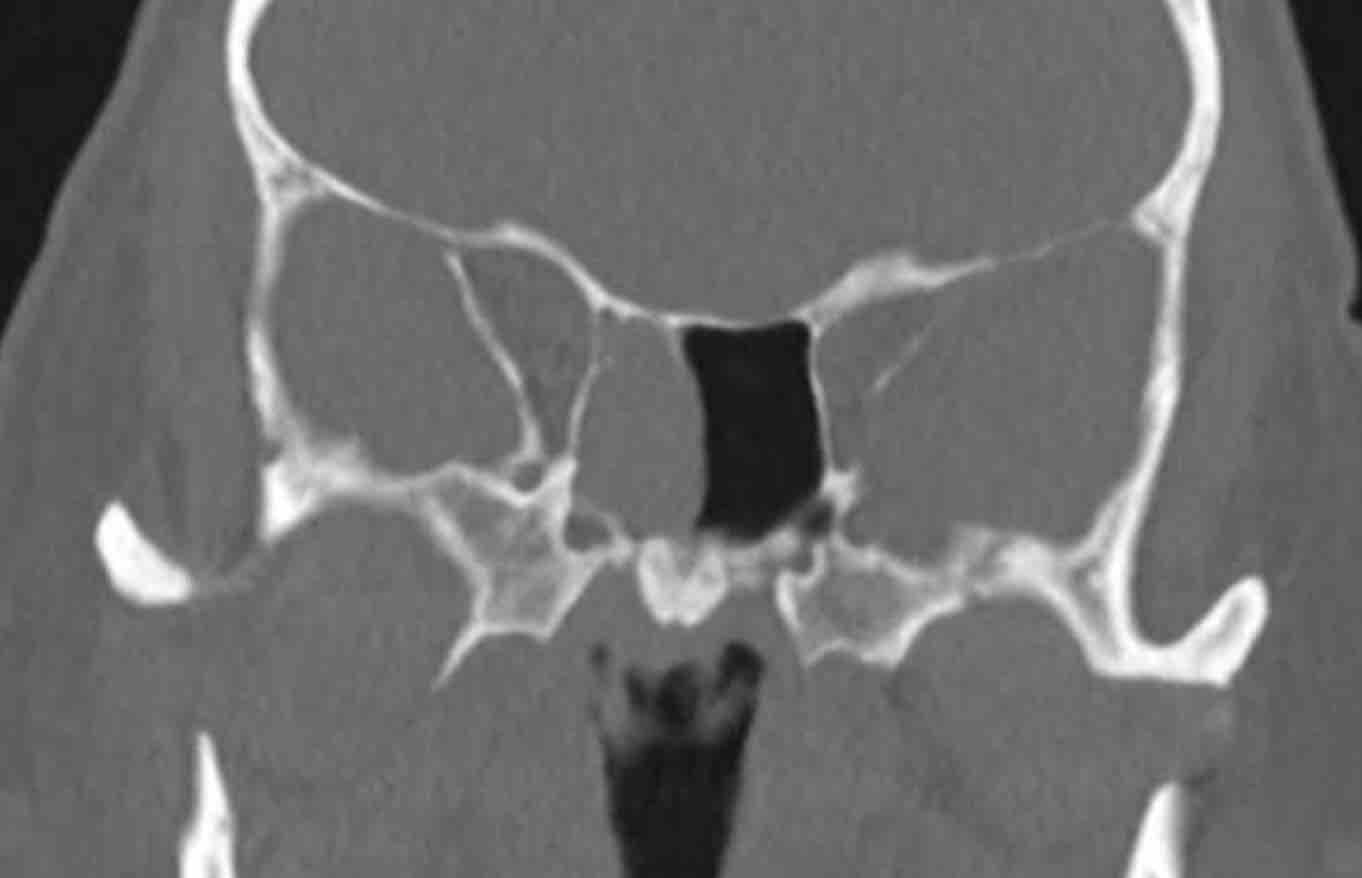

Hình ảnh

Có hình ảnh thấu quang quanh chóp răng tại vùng chân răng hàm lớn trên bên phải, gợi ý nhiễm trùng răng (đầu mũi tên đen).

So sánh với bên trái bình thường trên ảnh cắt ngang (đầu mũi tên trắng).

Thăm khám lâm sàng bổ sung đã loại trừ tổn thương ác tính.

Bệnh nhân được chuyển khám răng hàm mặt vì nhiễm trùng răng hoàn toàn có thể là nguyên nhân gây viêm xoang mạn tính một bên.

Lưu ý: Vì lý do này, việc bao gồm vùng xương hàm trên trong trường chụp của CT xoang là điều hết sức quan trọng.